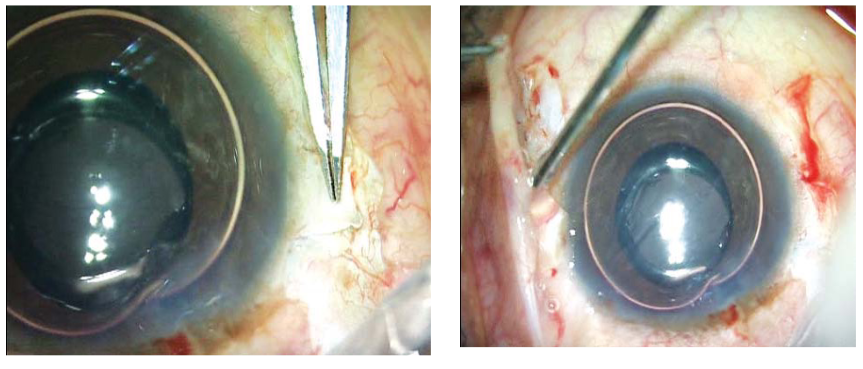

图1A和B:距离角膜缘1.5mm处制作约2.5*3mm的巩膜瓣。两个瓣成180°对角相对。